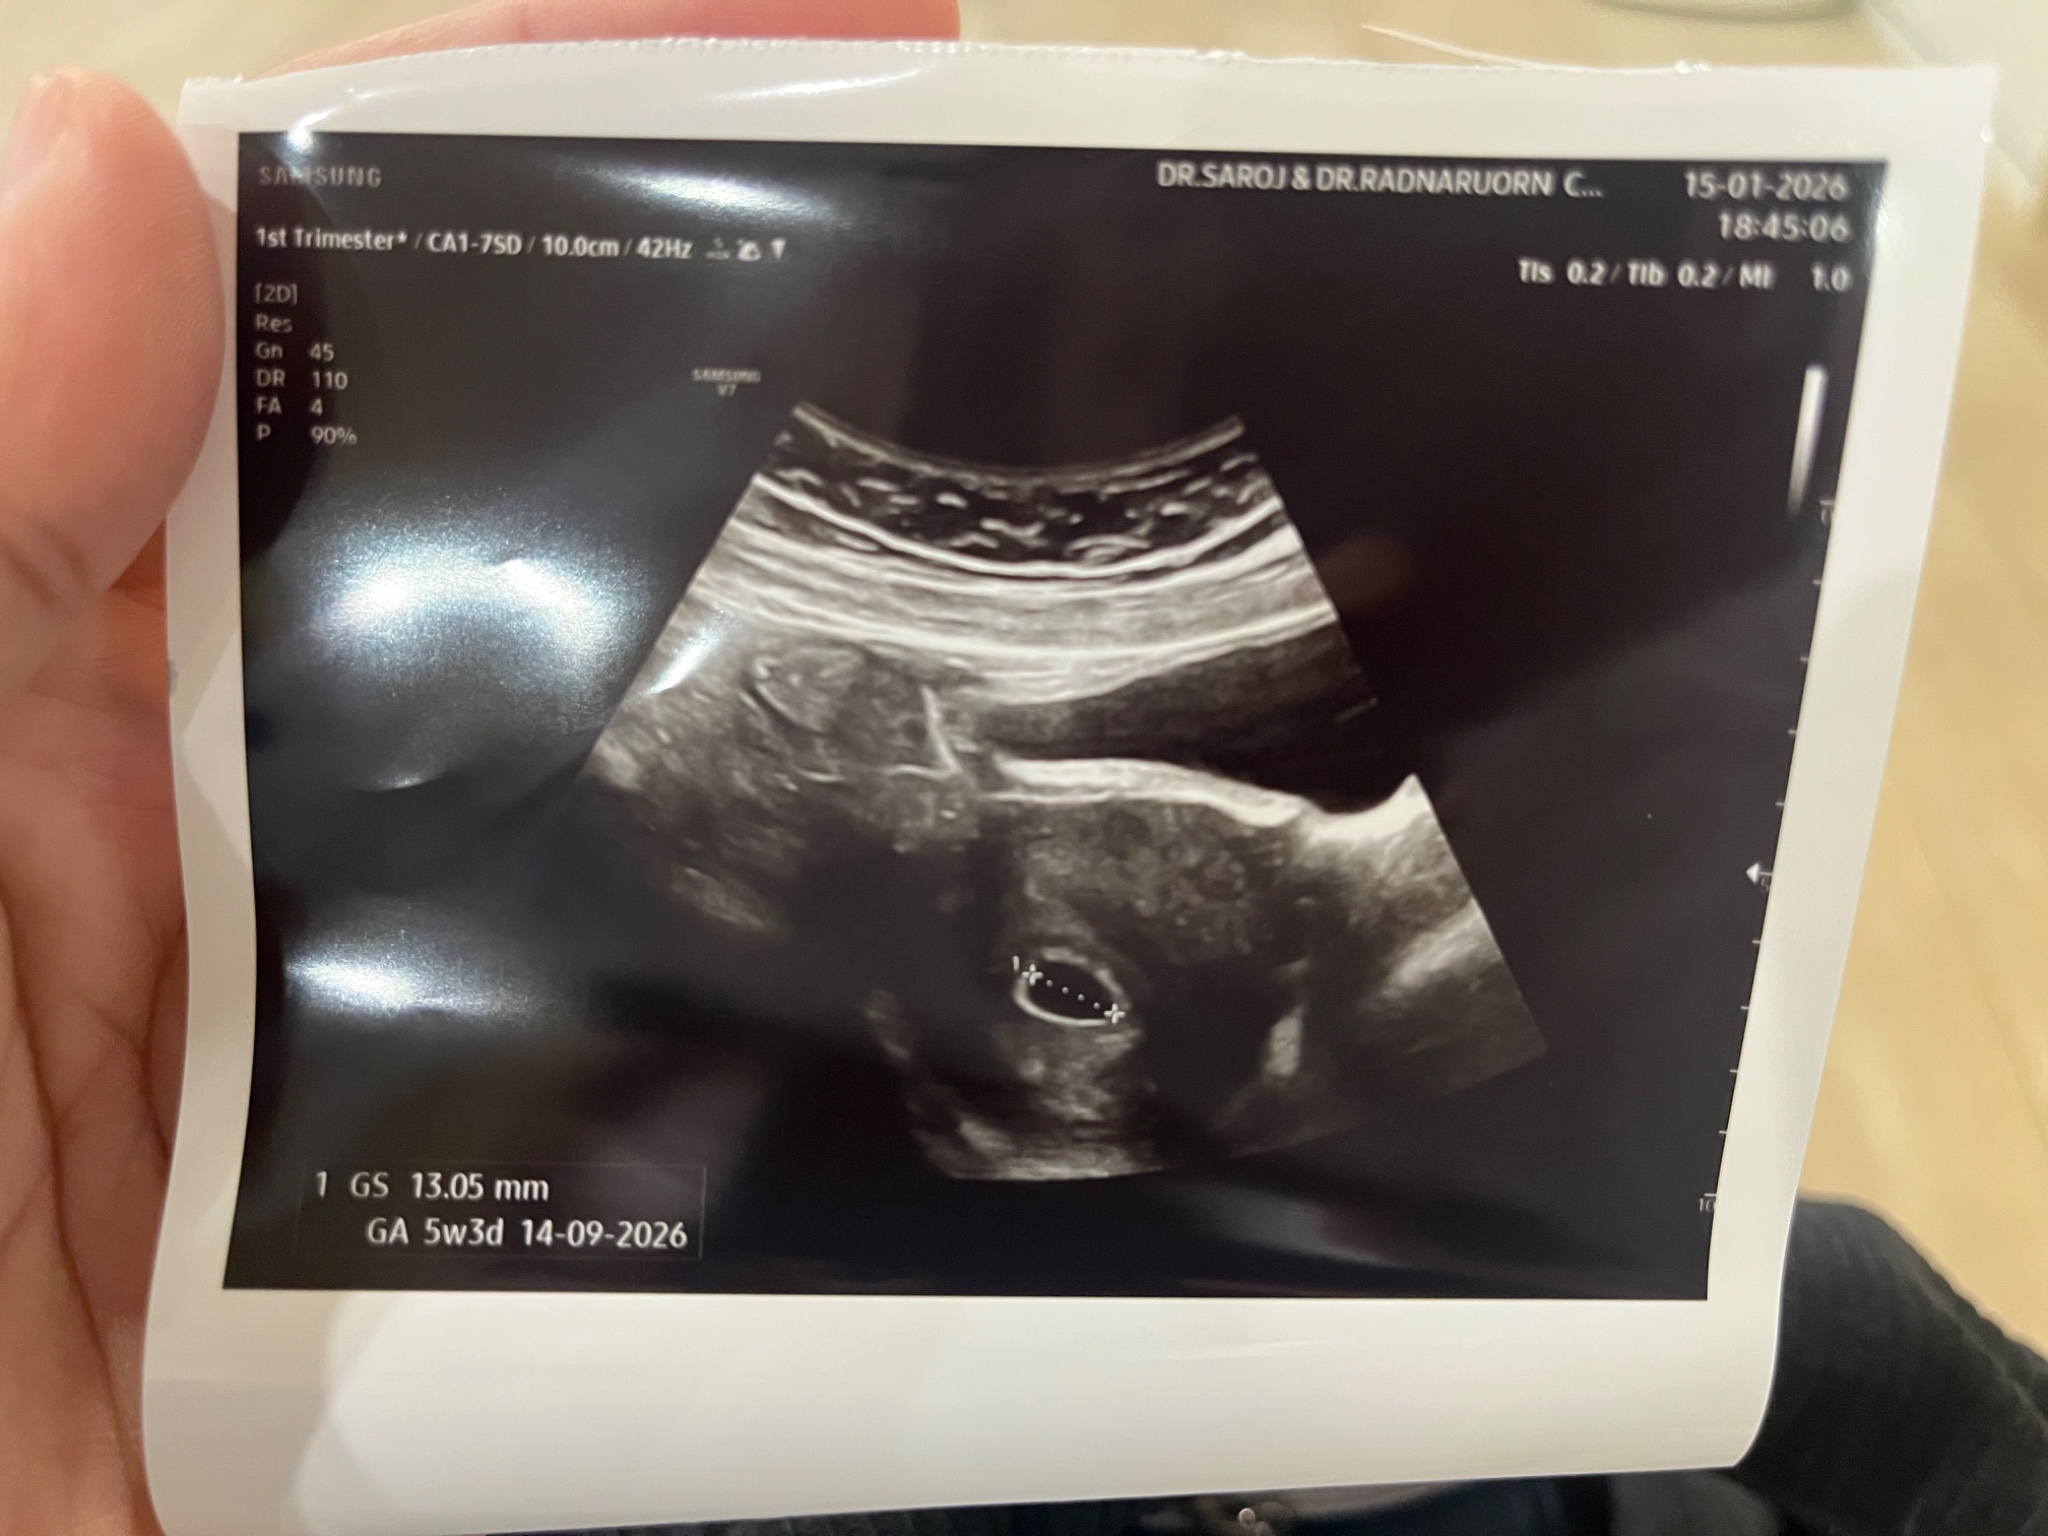

-ไปคลินิกตรวจครรภ์ วันที่ 15/01/69 อายุครรภ์ 5 สัปดาห์ 3 วัน เอาฟิล์มและใบรับรองแพทย์มา เสียเงิน 1,100 บาทคลินิกใกล้บ้าน